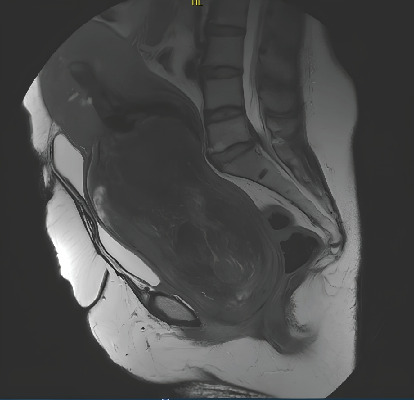

We report the case of a 57-year-old woman who presented to the gynecological emergency department with an enormous 18 cm submucosal leiomyoma pedunculated through the cervix. She was anemic due to bleeding over the past 2 months. The aim of this study was to highlight the challenges of managing such an unusual clinical scenario. We also describe the preoperative and intraoperative methods that can be used to minimize intraoperative blood loss and improve the safety and feasibility of this kind of surgical procedure. In our case, we decided to perform a vaginal myomectomy after a tourniquet on the pedicle to reduce bleeding.